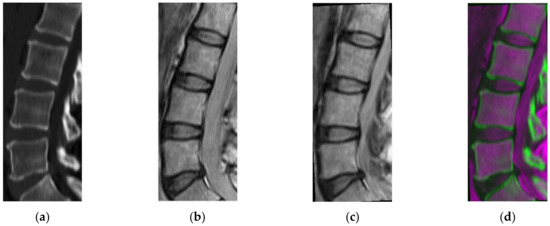

2.3. Vertebral Region Projection on MRI

2.6. CT/MRI Image Fusion